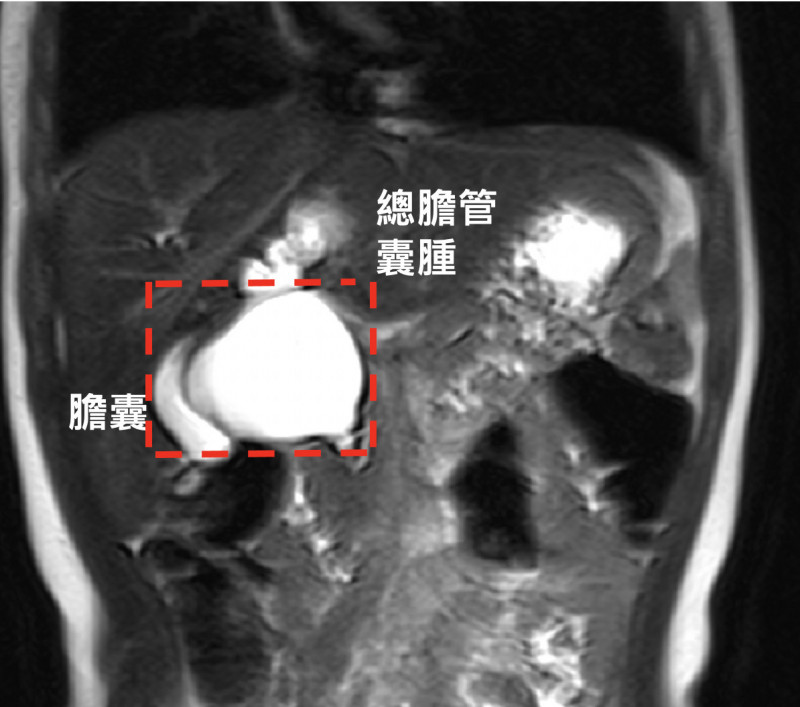

〔記者蔡淑媛/台中報導〕2歲盧小妹今年做檢查時意外發現罹患總膽管囊腫,米粒大小的總膽管已腫脹如乒乓球,如果不盡早手術切除,恐會黃疸、反覆膽道發炎、胰臟發炎,以及肝硬化,甚至惡化罹癌,6月接受用單孔達文西手臂手術切除總膽管囊腫與膽道重建,恢復健康,明天滿2歲,今天開心與治療團隊提早過生日。

台中榮總外科部主任、兒童外科醫師周佳滿指出,總膽管囊腫為先天性膽管異常疾病,會造成膽汁排出受阻,引發腹痛、發燒、黃疸、灰白便等症狀,嚴重會併發膽道結石、肝功能異常、胰臟炎,在台灣發生率約為千分之一,大多在兒童6、7歲前發病,若不手術切除,數10年後可能惡化為膽管癌,即便完全切除病灶,仍存在約4%的癌化風險,需要長期追蹤。